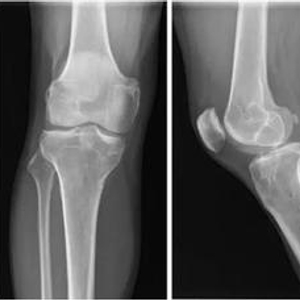

术后影像学显示移植半月板已填充在正常位置,匹配良好